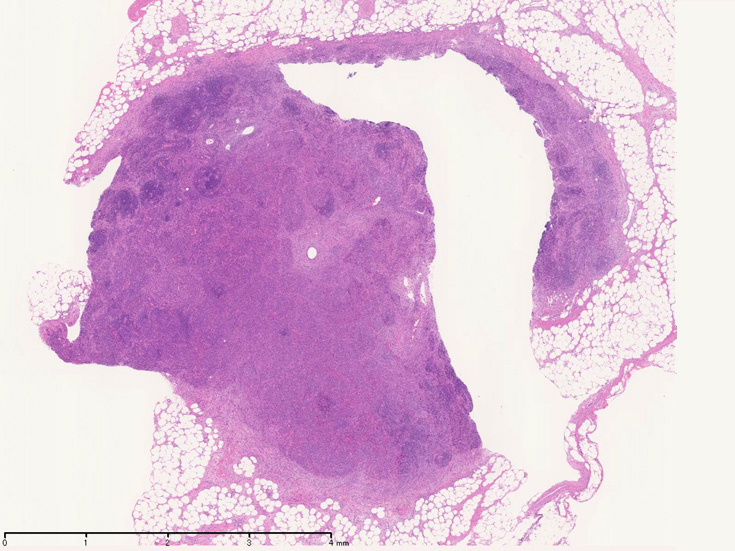

開腹リンパ節生検(腹膜脂肪組織内リンパ節, 割が入っている)

腹膜脂肪組織内から生検されたリンパ節は基本構造を失っている。低倍率のHE所見では異型細胞が不鮮明な結節構造を形成して増殖している。一次リンパ濾胞を腫瘍細胞が置換しているように見える所見がある。